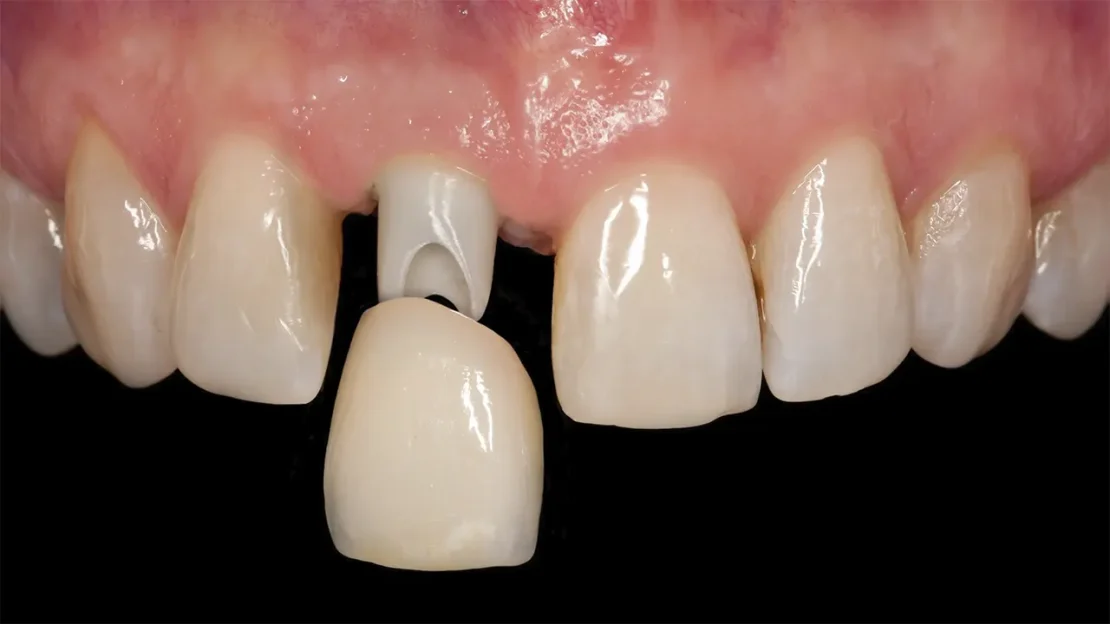

پروتکل نوع ۱: کاشت ایمپلنت فوری یا بلافاصله (Immediate Implant Placement)

در این روش، ایمپلنت دندان در همان جلسه و بلافاصله پس از کشیدن دندان، در داخل حفره تازه ایجادشده قرار می گیرد.

| شرایط لازم و محدودیت ها | حفره دندان باید کاملاً سالم و بدون هیچ گونه عفونت حاد یا کیست باشد. تمام دیواره های استخوانی حفره باید سالم و دست نخورده باشند. ایمپلنت باید در استخوان انتهای حفره به گیر و ثبات اولیه بسیار بالایی دست یابد. وجود لثه سالم و ضخیم. |

| کاربرد اصلی | بیشتر در دندان های جلویی (ناحیه زیبایی) که حفظ فرم لثه و استخوان اهمیت فوق العاده ای دارد. |